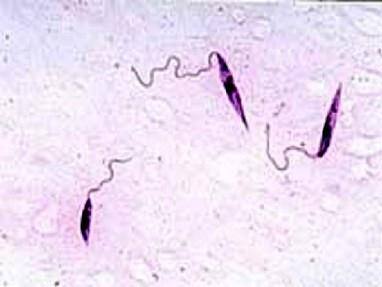

问题 图为杜氏利什曼原虫生活史的前鞭毛体阶段, 下列关于前鞭毛体说法错误的是 ( )

选项 A.见于白蛉消化道 B.在22℃~25℃培养基中呈纺锤形,前端有一游离鞭毛 C.在22℃~25℃培养基中大小约11~16μm D.在22℃~25℃培养基中长度与体长相仿 E.抵抗力强,80℃可存活6月,胃液中可耐受24h

答案 E